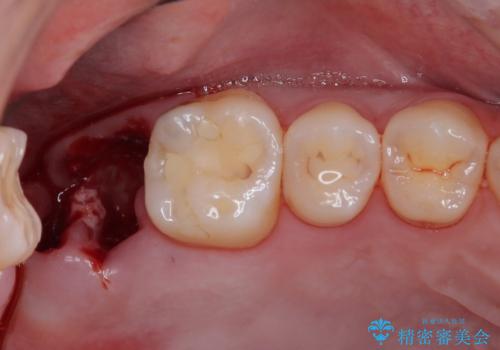

- 過去の歯医者通いの恐怖から虫歯を放置してきたものの、一大決心して来院された患者様です。

神経組織の失活している歯や歯根だけが残っている歯などがあり、全体的に歯石も多く付着している状態でした。

まずは歯石除去とブラッシング方法などの衛生指導を徹底的に行って口腔内環境を改善し、汚れの溜まりやすくなっている親知らずは全て抜去することとしました。

その後、歯根だけとなっている歯はインプラントに、神経組織の失活している歯は根管治療を行い、いずれもオールセラミッククラウンにて補綴治療を行うこととしました。

右上のインプラント治療は、1DAYインプラント治療(抜歯即時埋入・即時荷重)の適応となりましたので、通常3回必要な外科処置の回数を1回に集約させることができました。